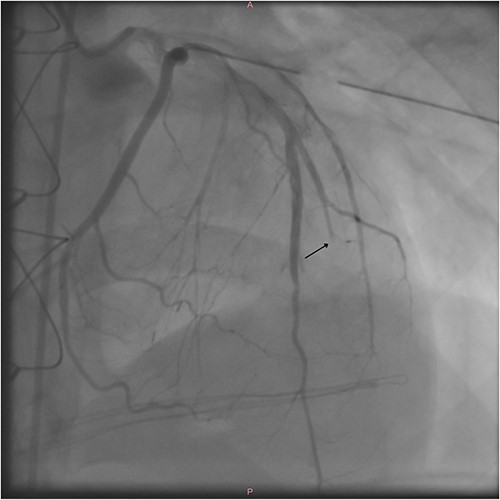

After the procedure, the patient was hemodynamically stable and transported to the ICU. Postoperative coronary angiogram showed a transected second diagonal branch of LAD (Fig. 3).

Postoperative coronary angiography shows a transected second diagonal branch of the LAD (arrow).